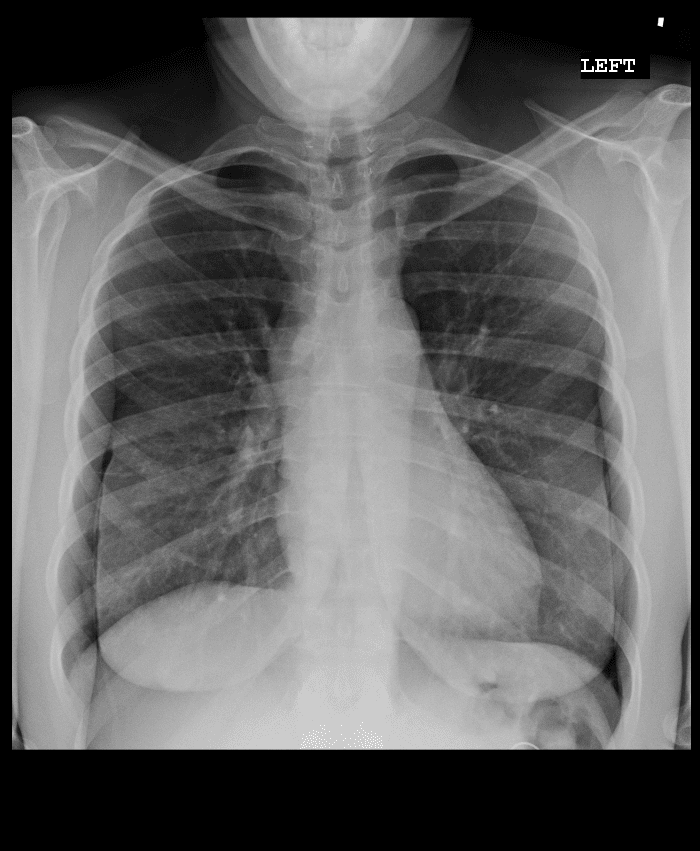

Practice Cases